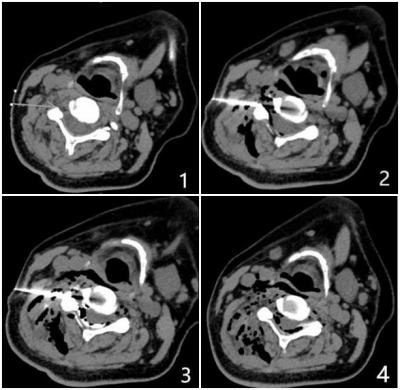

Figure 2. Male, 38 years old, with intractable hiccup for 3 months, 3.0 T MR brachial plexus imaging showed that the signal of the left fourth cervical nerve was obviously increased.